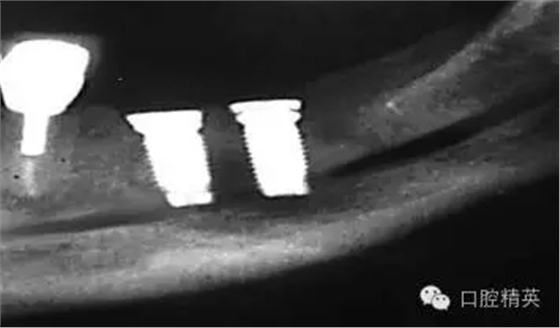

圖7a:6,7號(hào)牙種植體(3*15mm)折斷前,從物理學(xué)理論上講,種植體骨整合后,基臺(tái)螺絲和種植體相連接的支點(diǎn)處是受力時(shí)種植體最薄弱的位置。(a)可見(jiàn)6號(hào)牙種植體的折斷面,和7號(hào)牙種植體上的折裂線(b)。

圖7b:6,7號(hào)牙種植體折斷后。

圖7c,d:6,7號(hào)牙的回顧性模型分析顯示為了獲得滿意的美學(xué)效果牙冠不得不做的很長(zhǎng),從而形成較深的咬合關(guān)系。同時(shí)可見(jiàn)對(duì)頜牙磨耗嚴(yán)重,廣泛。

種植體折斷可能發(fā)生于種植體行使功能幾年后,也可能發(fā)生于早期。(圖7a,b)對(duì)于圖中這一病例,治療計(jì)劃是在對(duì)患者的咬合關(guān)系,未來(lái)修復(fù)體理化環(huán)境,患者咀嚼習(xí)慣等充分評(píng)估后制定的。種植體折斷后,對(duì)該病例進(jìn)行了回顧性病因分析,上了頜架的模型揭示了過(guò)長(zhǎng)的頜間距離,和嚴(yán)重、廣泛的對(duì)頜牙磨耗(圖7c,d)。對(duì)于這一病例,醫(yī)生仔細(xì)評(píng)估了所有可得到的回顧性診斷信息,和患者進(jìn)一步討論交流后,提出了幾個(gè)診斷建議和一個(gè)過(guò)渡性治療方案,其中包括將固定修復(fù)改為鑄造可摘局部義齒。

考慮到取出種植體會(huì)造成很大的創(chuàng)傷,醫(yī)生提出了一個(gè)盡量避免增加創(chuàng)傷風(fēng)險(xiǎn)的折中治療方案。治療為:嚴(yán)密縫合關(guān)閉6號(hào),7號(hào)牙種植體周圍軟組織,將種植體埋入休眠。術(shù)后即刻戴入塑料過(guò)渡活動(dòng)義齒,術(shù)區(qū)軟組織穩(wěn)定后進(jìn)行鑄造可摘局部義齒修復(fù)。

這個(gè)病例似乎支持了物理機(jī)械原因可能導(dǎo)致種植體折斷的理論。冠根比是否和牙齒的預(yù)后相關(guān),修復(fù)體-種植體長(zhǎng)度比例是否和種植體成功直接相關(guān)仍是一直在爭(zhēng)論的話題;但它和其他一些因素,如咬合關(guān)系不良,口腔副功能存在或材料存在電化學(xué)缺陷等,合并時(shí)確實(shí)會(huì)影響天然牙或種植體的健康。